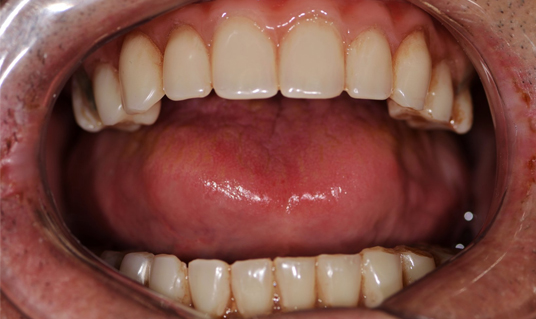

Сразу после операции изготовленный протез фиксируется к имплантам на винты. По завершению операции, можно сразу давать нагрузку на протез. Теперь вы можете есть, говорить и улыбаться совершенно ничего не стесняясь.

Результаты лечения

Вы получите естественную и привлекательную улыбку

Измените свою жизнь

Вернёте уверенность и молодость

Навсегда забудете о неудобстве съемных протезов